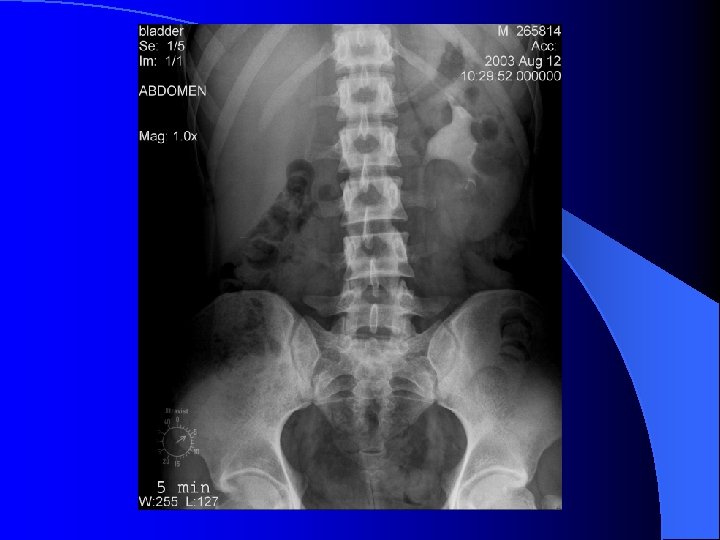

UIV l Timp parenchimatos – nefrograma – sub 1 min. de la terminarea injectării – nefrotomografie l Timp excretor – urograma – ~ 3 min. de la terminarea injectării – opacifierea căilor excretorii – uzual clişee la 5, 15 şi 30 min.

UIV - variante NU EXISTĂ UIV STANDARD!!! l Compresie ureterală – zona iliacă l – opacifiere optimă a SPC şi ureterelor – contraindicaţii – colica renală – traumatismele aparatului urinar – anevrism aorta abdominală Decubit ventral –rezultate similare compresiei l Încărcare cu apă – ingestie 500 ml lichid/furosemid 40 mg i. v. – disfuncţia de joncţiune l Clişeu postmicţional – rezidiu l UIV minutată l

Modificări morfologice – căi excretorii - dimensiuni l Dilataţia l – creştere de diametru/volum SPC – dilataţie globală = hidronefroză – calice: contur extern drept/convex – tije caliceale: diametru crescut – bazinet: contur inferior convex Ureter – asociază dilataţie SPC = ureterohidronefoză l Vezică urinară – apreciată prin rezidiul postmicţional l – obstrucţie acută – contururi neregulate (“vezica de luptă”) – obstrucţie cronică – volum > 500 ml l Cauze – sindromul obstructiv